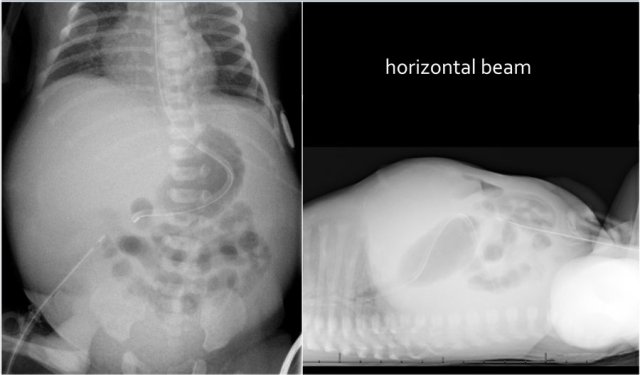

The findings are:

- The abdominal radiograph shows the triple bubble sign without distal bowel gas.

- Abdominal calcifications

Diagnosis:

Jejunal atresia and in utero perforation with meconium peritonitis.